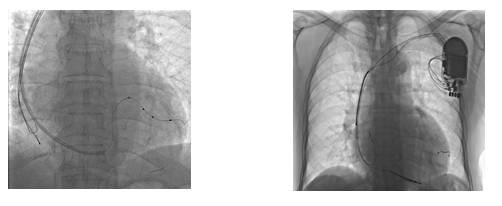

三、无导线起搏技术

[2]

2014年Auricchio等报道了首个无导线左心室心内膜起搏电极应用于人体进行再同步化治疗的WISE-CRT研究(results of the Wireless Stimulation Endocardially for CRT study)

左室无线电级植入示意图

共纳入17例心力衰竭患者,随访6个月时

--双心室起搏比例为92%

--QRS波时限较右心室起搏减少42ms

--约2/3患者心功能分级较前改善一级

--EF较前升高

--无血栓事件

优势

◆避免了导线相关的并发症

◆更低且稳定的起搏阈值,更多可选择的起搏位置

◆主动固定电极的稳定性优于传统植入方式

◆减少膈肌刺激

◆心内膜起搏使心脏除极更接近生理情况

与有导线技术相比的优势

◆电极尺寸小

◆聚酯外套提高内皮化,利于避免血栓风险

◆电极稳定性相对更好

◆不跨越二尖瓣,无二尖瓣反流等相关并发症

局限性

◆缺血性心肌病左心室瘢痕有起搏不成功的可能

◆手术技术及相关设备还不够成熟,WISE-CRT研究中17例患者中有3例发生急性心包填塞,电极植入未成功

◆没有导线连接,难以直接评估左心室电极的各项参数

◆有血栓的风险